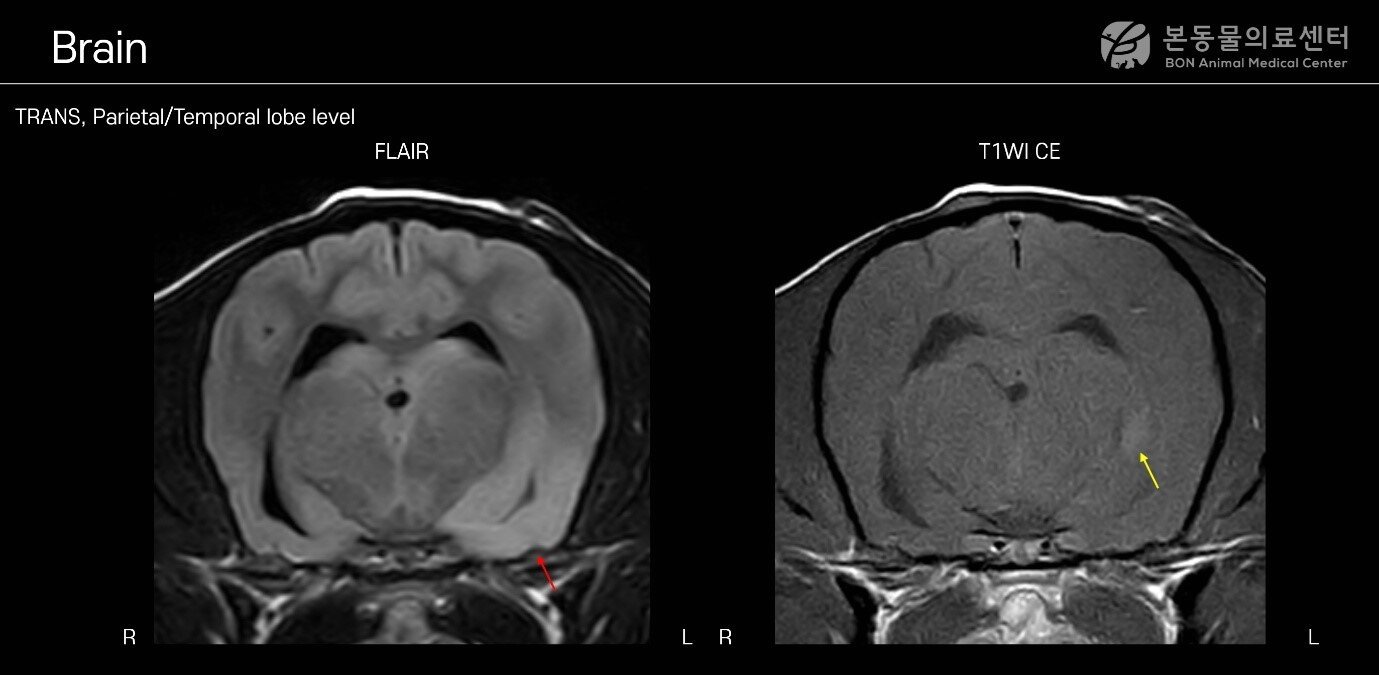

본문 이미지 - MRI 검사 결과 염증 부위를 확인할 수 있는 사진(본동물의료센터 제공) ⓒ 뉴스1

MRI 검사 결과 염증 부위를 확인할 수 있는 사진(본동물의료센터 제공) ⓒ 뉴스1